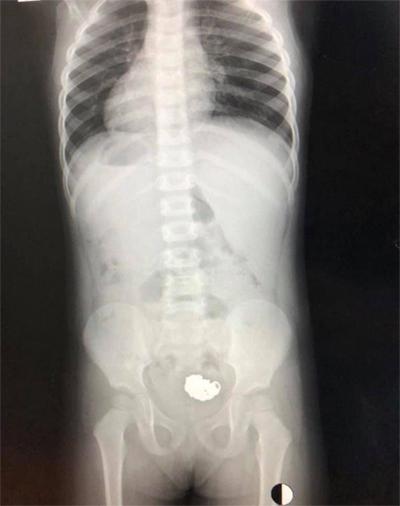

Hình ảnh X-quang cho thấy chiếc vòng đã "an vị" tại ruột già, sau khi đã đi qua thực quản, dạ dày, môn vị, xuống tá tràng…

Hình ảnh chụp xquang

Do hình ảnh chiếc vòng đã được cuộn tròn, vón cục lại, đặc biệt là hình dáng của chiếc vòng này lại không có cạnh sắc nên loại bỏ khả năng làm tổn thương cơ quan tiêu hóa của bé.